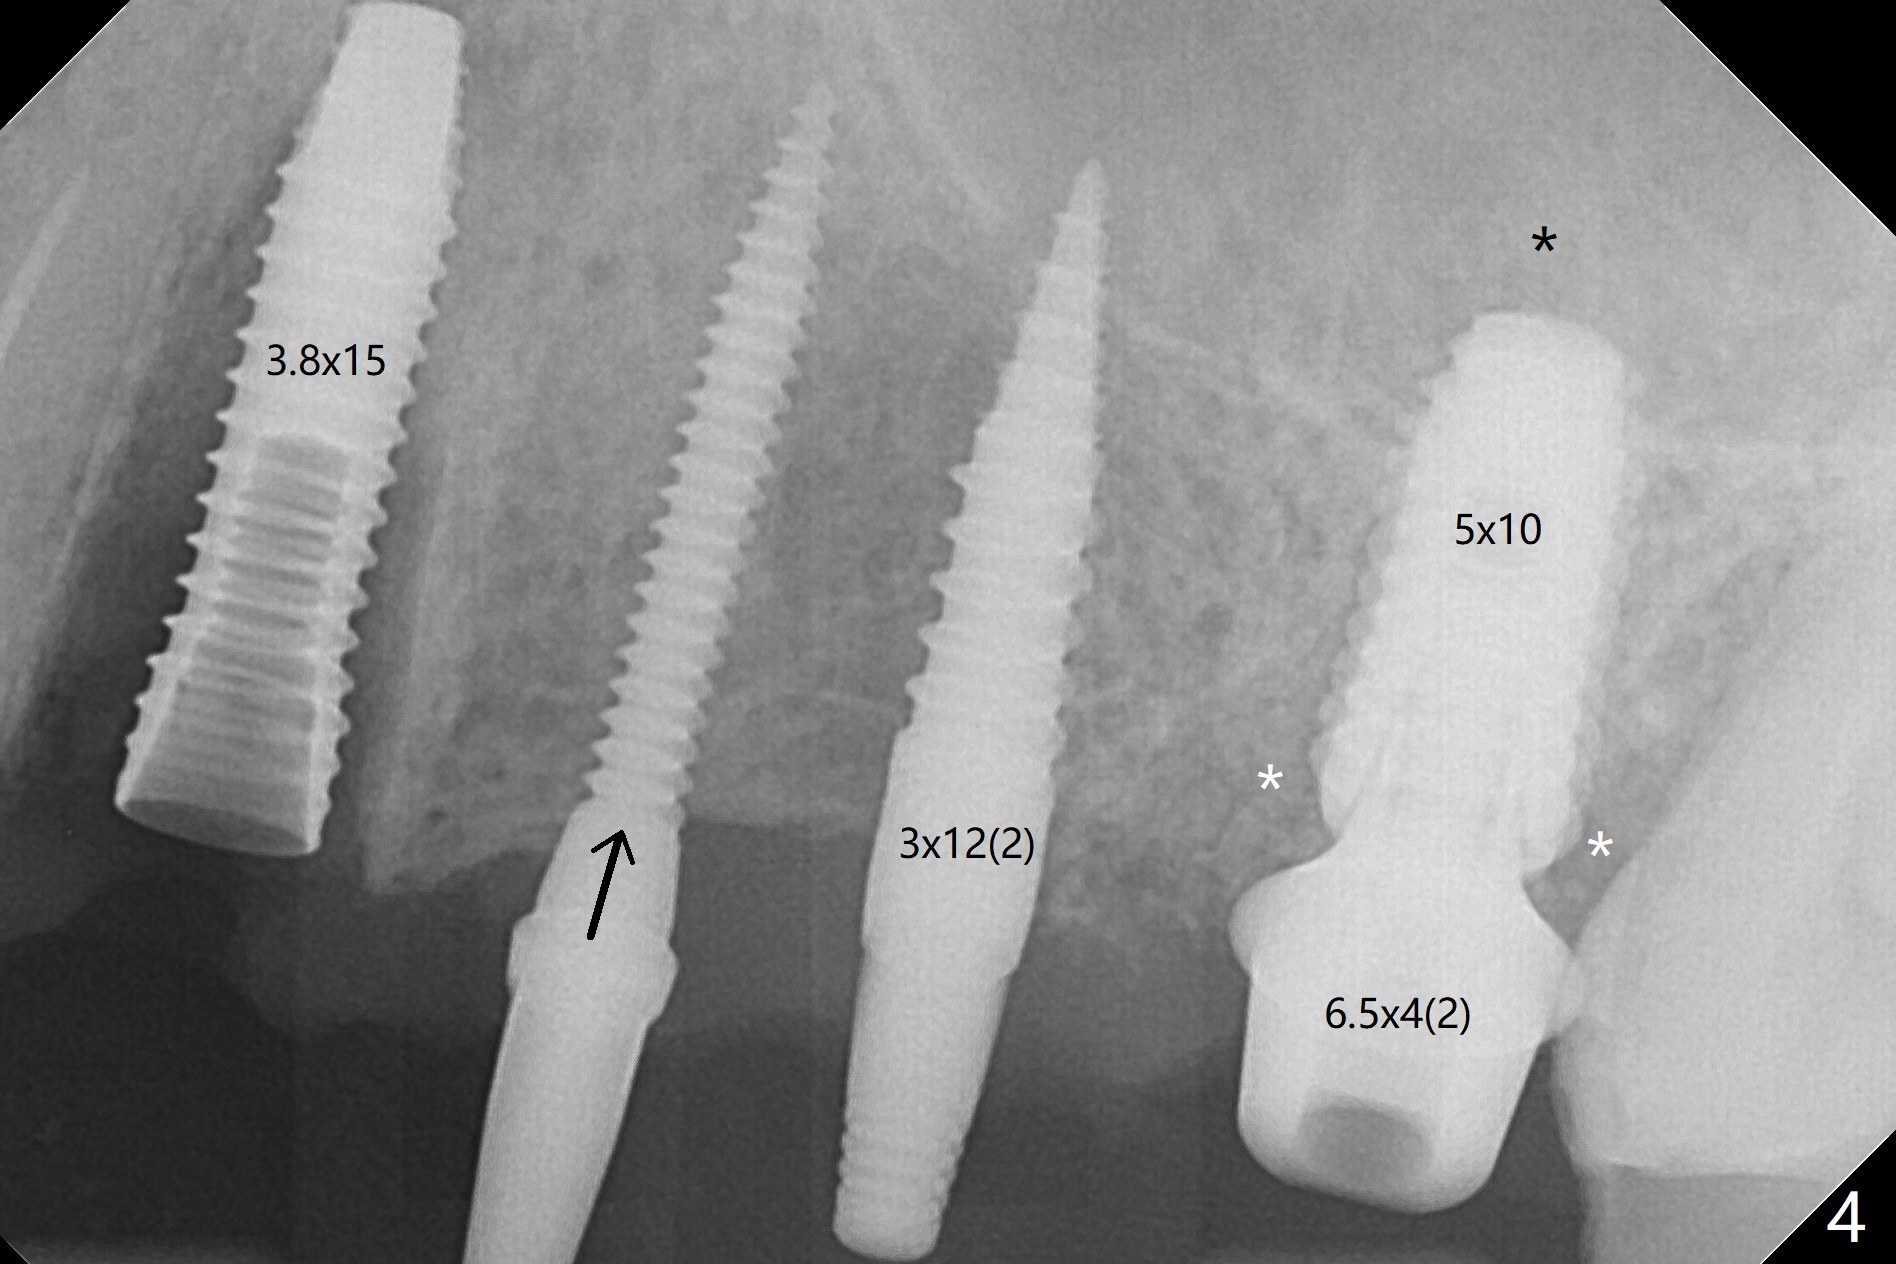

The edentulous ridge is narrow between the residual roots of #11 and 14 (Fig.1). Since the bone density is low in the edentulous area, DIO bone expanders are used (e.g., #1 (1/1.6 mm) Fig.2) after 1.2 mm initial drill. A 2x14(2) mm 1-piece implant is placed at #12 with 4 mm ridge width, while a 3x10 (2) mm dummy implant is partially placed after use of Bone Expander #2 (1.3/2.3 mm). The latter is replaced by a definitive one (3x12(2) mm), while the one at #12 is placed deeper (Fig.4). After extraction and placement of PRF and Vanilla Graft for sinus lift (Fig.4 black *), a 5x10 mm 2-piece implant is placed at #14, while a dummy implant is placed at #11 (Fig.4,5). As the osteotomy at #11 is 4.9 mm longer than the dummy (Fig.5), a definitive one is 3 mm longer (Fig.6). Osteogen plug is placed in the apical portion of each socket at #11 and 14, while Vanilla and Osteogen are packed in the coronal portion of the socket (Fig.4,6 *). Although primary stability of each implant is not high (30/40 Ncm), splinted provisional with occlusal clearance seems to be sufficient for implant osteointegration. There is no discomfort 9 days postop (Fig.7). Impression is taken 3 months postop, since he plans to return to home country for business (Fig.8). Single unit crowns are cemented 4 months postop (Fig.9,10). The abutment screw at #14 needs retightening 6 months post cementation. The access hole slightly buccal. Chewing pain at #12 is reduced after occlusal adjustment 6.5 months post cementation (Fig.11).